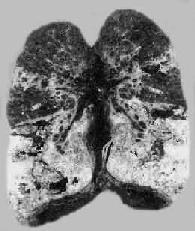

图18-6 肺结核支气管播散 图中箭头示干酪化的气管分叉淋巴结溃穿支气管,引起两侧小叶性干酪样肺炎及空洞形成 肺结核原发综合征恶化进展发生血道播散时,引起的血源性结核病有以下三种类型: 1)全身粟粒性结核病:当肺原发灶中的干酪样坏死灶扩大,破坏了肺静脉分支,大量结核杆菌由肺静脉经左心至大循环,可播散到全身各器官如肺、脑、脑膜、肝、脾、肾等处,形成粟粒性结核,称为急性全身性粟粒性结核病。肉眼见各器官内密布大小一致、分布均匀、灰白带黄、圆形的粟粒大小之结核结节。镜下,可为含菌较少的增生性病变,也可为含菌很多的渗出、坏死性病变。临床上,病情危重,有高热、衰竭、食欲不振、盗汗、烦躁不安等明显中毒症状,肝脾肿大,常有脑膜刺激征。若能及时治疗预后仍属良好,少数病例可因结核性脑膜炎死亡。 在机体抵抗力极差或用大量激素、免疫抑制药物或细胞毒性药物后,可发生严重的结核性败血症,为最剧烈的急性血源性全身性结核病,患者常迅速死亡。尸检时,在各器官内见无数小坏死灶,灶内含很多结核杆菌,灶周几乎无细胞反应可见,因而有无反应性结核病之称。此种病人可出现类似白血病的血像,称类白血病反应(leukemoid reaction)。 2)肺粟粒性结核病:又称血行播散型肺结核病。急性粟粒性肺结核病常是全身粟粒性结核病的一部分。偶尔,病变也可仅局限于两侧肺内。这是由于支气管周围肺门或纵隔淋巴结干酪样坏死破入附近的静脉(如无名静脉、颈内静脉、上腔静脉),含大量结核菌的液化物经右心和肺动脉播散至双肺所引起。肉眼观,双肺充血,重量增加,切面暗红,密布灰白或灰黄色粟粒大小的结节,微隆起于切面(图18-7),并显露于肺膜表面。

图18-7 肺粟粒性结核病 图中白色点状病灶为粟粒性结核灶 慢性粟粒性肺结核病多见于成年人,这时肺原发综合征业已钙化痊愈,结核杆菌由肺外(骨关节、泌尿生殖道及肾上腺等处)结核病灶较长期、间歇性地进入血流,播散于肺内,形成新旧不等的病变。间隔时间可为数月甚至数年。患者多因结核性脑膜炎死亡。 3)肺外器官结核病:或称肺外结核病,大多是原发性肺结核病经血道播散的后果。在原发综合征期间如有少量结核杆菌经原发灶内的毛细血管侵入血流,则能在肺外某些器官(骨关节,泌尿生殖器官、神经系统、浆膜、皮肤等)内形成个别的结核病灶。这些病灶可自愈或潜伏下来,经过较长时间后,当机体抵抗力下降时乃恶化进展为肺外器官结核病。 (二)继发性肺结核病 继发性肺结核病(secondary pulmonary tuberculosis)是指再次感染结核菌所引起的肺结核病,多见于成年人,故又称成人型肺结核病。肺内的病变常开始于肺尖,称再感染灶。关于再感染灶的形成机制有以下两种学说:①外源性再感染学说,认为继发性肺结核的发病是由外界重新感染所致,与原发性肺结核无任何联系;②内源性再感染学说,认为继发性肺结核病的再感染灶大多是由原发性肺结核病血源性播散时在肺尖部形成的病灶。在机体免疫力下降时,潜伏的病灶可发展为继发性肺结核病。此外,也可是肺内未愈合的原发灶内的结核菌经小支气管蔓延或由肺外器官结核病灶内的结核菌经血道播散至肺的结果。 继发性肺结核病患者对结核杆菌已有一定的免疫力或过敏性,所以继发性肺结核病与原发性肺结核病的病变有以下不同特点:①病变多从肺尖开始,这可能与人体直立位时该处动脉压低、血循环较差,随血流带去的巨噬细胞较少,加之通气不畅,以致局部组织抵抗力较低,细菌易在该处繁殖有关。②由于变态反应,病变发生迅速而且剧烈,易发生干酪样坏死,同时由于免疫反应较强,在坏死灶周围每有以增生为主的病变,形成结核结节。免疫反应不仅能使病变局限化,而且还可抑制细菌的繁殖,防止细菌沿淋巴道和血道播散,因此肺门淋巴结一般无明显病变,由血源播散而引起全身粟粒性结核病者亦极少见。病变在肺内蔓延主要通过受累的支气管播散。③病程较长,随着机体免疫反应和变态反应的消长,临床经过常呈波浪起伏状,时好时坏,病变有时以增生性变化为主,有时则以渗出、坏死变化为主,常为新旧病变交杂。 因此,继发性肺结核病的病变和临床表现都比较复杂。根据其病变特点和临床经过可分为以下几种主要类型: 1.局灶型肺结核 病变多位于肺尖下2~4cm处,右肺较多。病灶可为一个或数个,一般约0.5~1cm大小,多数以增生性病变为主,也可为渗出性病变,中央发生干酪样坏死。如病人免疫力较强,病灶常发生纤维化、钙化而痊愈。临床上病人常无明显自觉症状,多在体检时发现,属无活动性肺结核一类。如病人免疫力降低时,可发展成为浸润型肺结核。 2.浸润型肺结核是临床上最常见的一种类型,属于活动性肺结核。大多是局灶型肺结核发展的结果,少数也可一开始即为浸润型肺结核。病变中央常有较小的干酪样坏死区,周围有广阔的病灶周围炎包绕。镜下,肺泡内充满浆液、单核细胞、淋巴细胞和少数中性粒细胞,病灶中央常发生干酪样坏死。病人常有低热、盗汗、食欲不振、全身无力等中毒症状和咳嗽、咯血等。痰中常可查出结核杆菌。如能早期适当治疗,一般多在半年左右可完全吸收或部分吸收,部分变为增生性病变,最后,可通过纤维化、包裹和钙化而痊愈。 如病人免疫力差或未及时得到适当治疗,病变可继续发展,干酪样坏死灶扩大(浸润进展期)。坏死物质液化经支气管排出后形成急性空洞,洞壁粗糙不整,内壁坏死层中有大量结核杆菌,坏死层外可有薄层结核性肉芽组织包绕。从空洞中不断向外排出含菌的液化坏死物质,可经支气管播散,引起干酪样肺炎(溶解播散)。如靠近肺膜的空洞穿破肺膜,可造成自发性气胸;如果大量液化坏死物质进入胸腔,可发生结核性脓气胸。急性空洞一般较易愈合,如能给以及时和强有力的抗结核治疗,这种空洞可通过洞壁肉芽组织增生而逐渐缩小,最终形成瘢痕而治愈,或通过空洞塌陷,形成索状瘢痕愈合。若急性空洞经久不愈,则可发展为慢性纤维空洞型肺结核。 3.慢性纤维空洞型肺结核为成人慢性肺结核的常见类型,多在浸润型肺结核形成急性空洞的基础上发展而来。病变特点是在肺内有一个或多个厚壁空洞形成。同时在同侧肺组织,有时也可在对侧肺组织,特别是肺下叶可见由支气管播散引起的很多新旧不一、大小不等、病变类型不同的病灶,部位愈下病变愈新鲜。空洞多位于肺上叶,大小不一,呈不规则形,洞壁厚,有时可达1cm以上。洞内常见残存的梁柱状组织,多为有血栓形成并已机化闭塞的血管。空洞附近肺组织有显著纤维组织增生和肺膜增厚(图18-8)。镜下,洞壁分三层:内层为干酪样坏死物质,其中有大量结核杆菌;中层为结核性肉芽组织;外层为增生的纤维组织。由于病情迁延,病变广泛,新旧不等,肺组织遭到严重破坏,可导致肺组织的广泛纤维化,最终演变为硬化型肺结核,使肺体积缩小、变形、变硬、肺膜广泛增厚并与胸壁粘连,可严重影响肺功能。